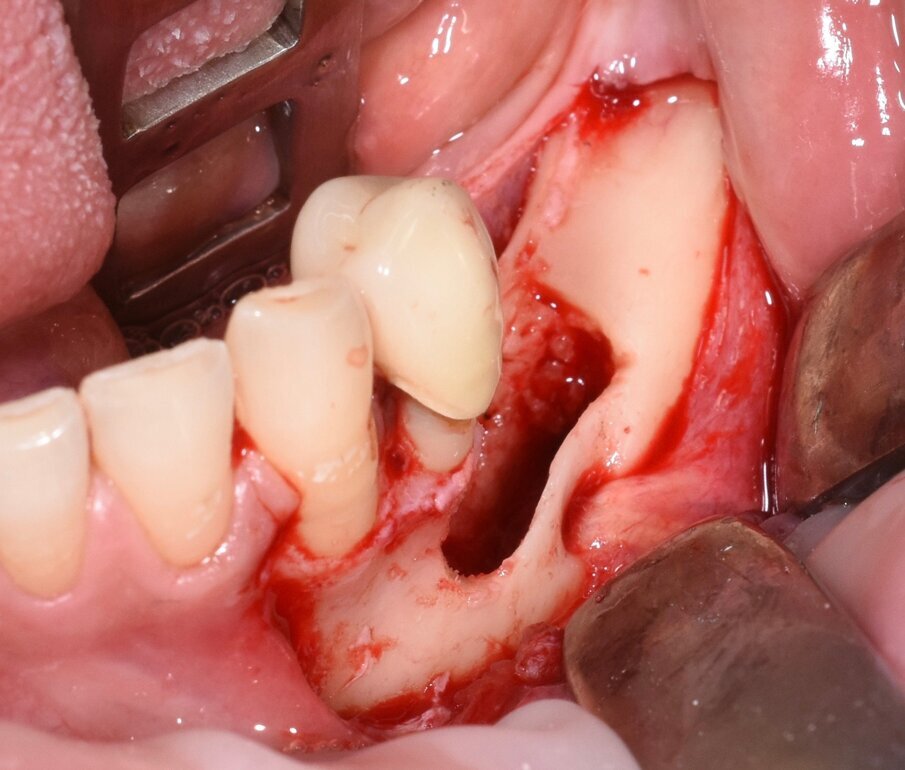

Fig. 9 - Rimozione della corona.

Fig. 10 - Cavità alveolare residua che evidenzia l’integrità del nervo mentoniero.

Considerata la necessità di eseguire un riabilitazione implantoprotesica della sede edentula si è resa necessaria l’avulsione dell’elemento incluso con tecnica piezoelettrica che ci ha permesso di ridurre al minimo l’osteotomia e preservare l’integrità del nervo la cui emergenza si trovava esattamente in corrispondenza della corona del 3.5 (Figg. 3-9).